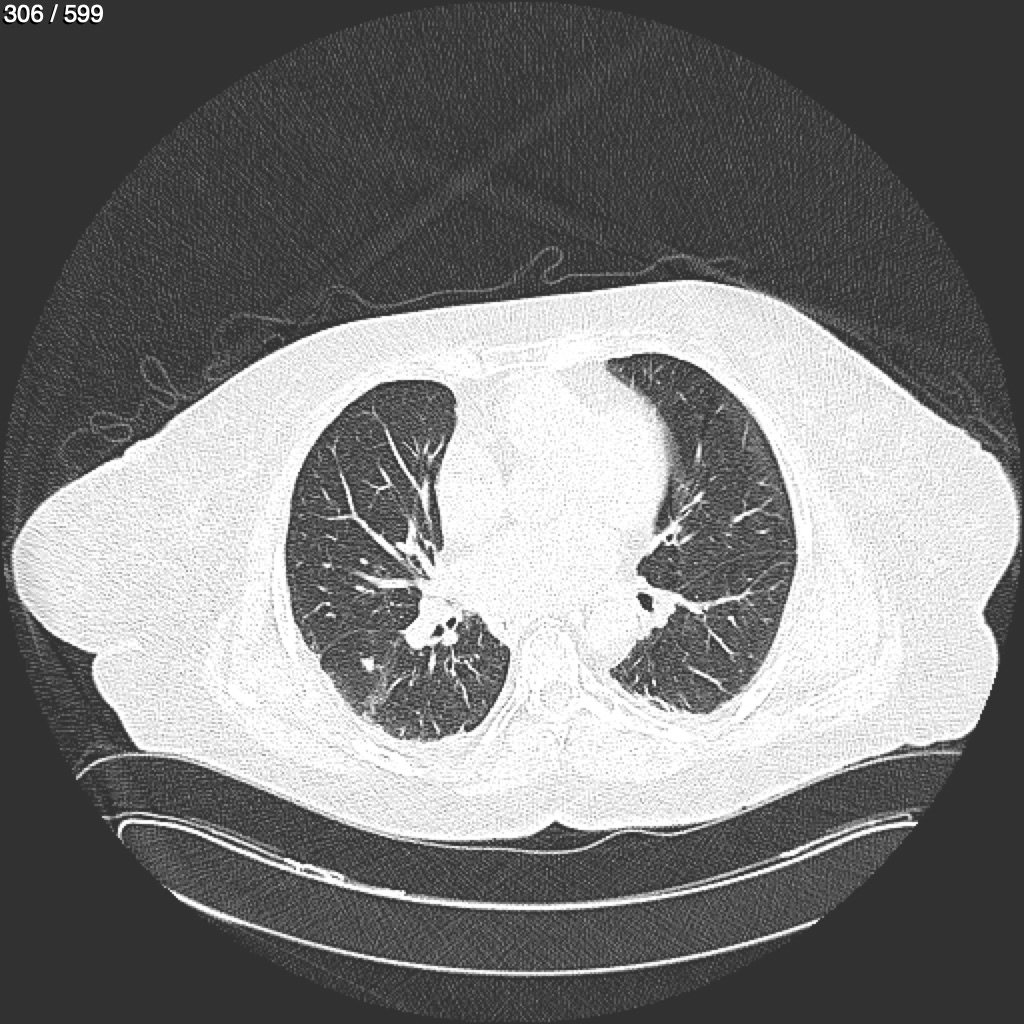

Home G​l​o​r​i​a​ ​G​l​a​d​y​s​ ​B​e​a​s​l​e​y​ ​-​ ​T​ó​r​a​x​ ​T​o​r​a​x​_​S​i​m​p​l​e​ ​(​A​d​u​l​t​o​)